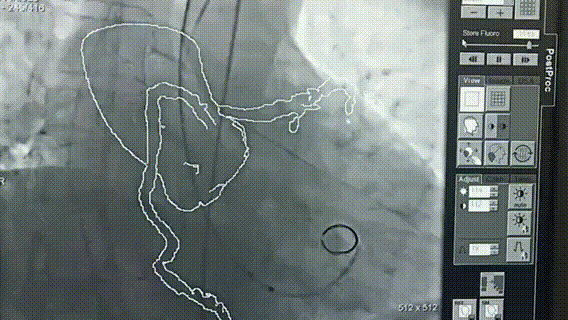

然而,随着定位-后释放技术的持续改进、杂交手术室的广泛建立、TAVR治疗经验的爆发式积累、新型弓部重建器具的出现,以及影像融合辅助技术的发展,升主动脉夹层微创腔内治疗的壁垒正在被逐一攻克。

术中影像辅助:经食管超声被证实为有效的术中辅助手段。